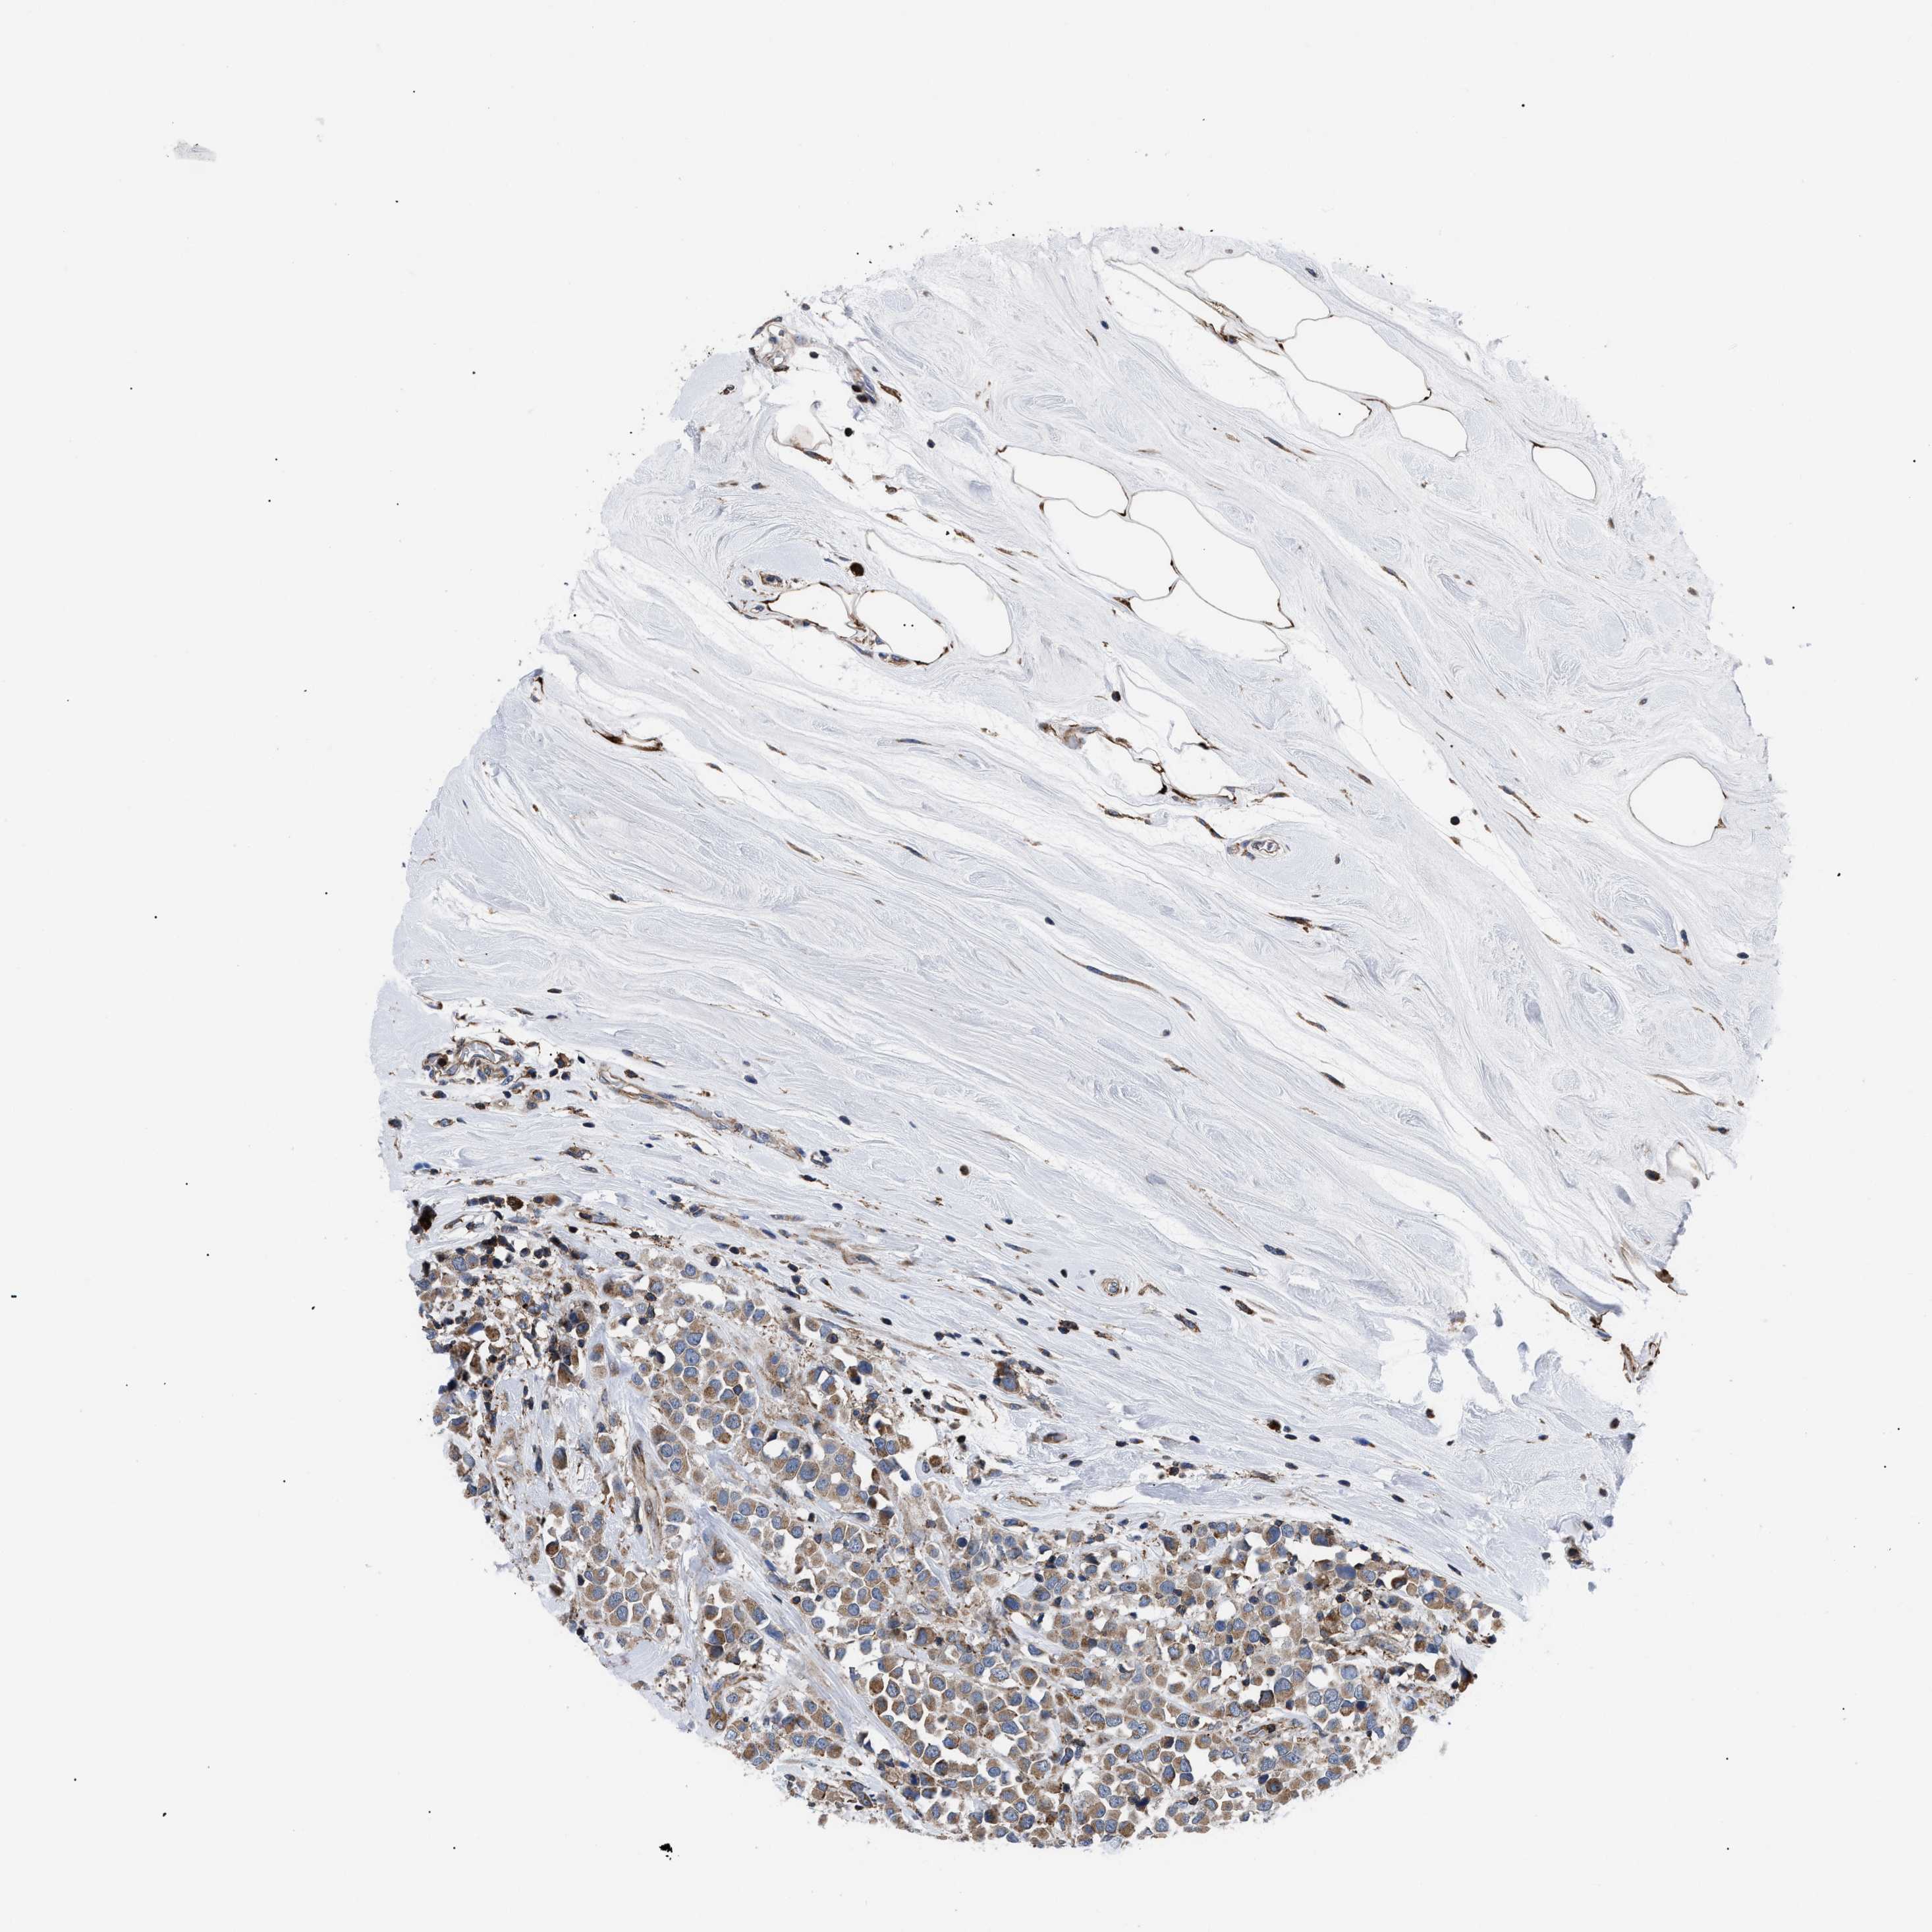

BRCA TCGA BRCA VALIDATION PROTEIN EXPRESSION

ANTIBODIES

AND

VALIDATION